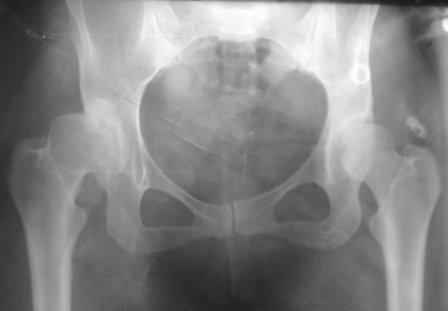

Типичная концовка проигнорированного диспластического состояния сустава. Дисплазия тазобедренного сустава часто встречающаяся патология у жителей Центральной Азии вследствие тугого пеленания в детстве. Традиционно ребенок находится в течение дня в так называемой кроватке "бешик", удобной в быту, но она впоследствии приводит к недоразвитию тазобедренного сустава.

Это первые признаки начала деструкции сустава, и возможно, аналгетики помогут для купирования болей, но в течение очень короткого времени от сустава ничего не останется, и в дальнейшем останется только артропластика.

Данный сустав в начальной стадии разрушения, но все-таки я бы сделал обзорный таз и отдельные снимки сустава в 30 градусной абдукции и аддукции. Также снимки с внутренней и наружной ротацией для оценки состояния головки бедра.